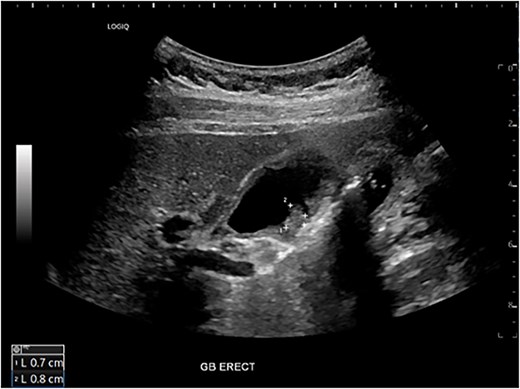

Six months after surveillance imaging, she was presented with ongoing abdominal pain. Liver function tests (LFTs) and Ca 19–9 remained normal at this time. A repeat abdominal US demonstrated an irregular gallbladder wall with thickening up to 5 mm and two stable gallbladder polyps, the largest measuring 7 × 8 mm (Fig. 2). Due to ongoing symptoms and changes on imaging, a laparoscopic cholecystectomy with intraoperative cholangiogram was performed without complication. At the time of surgery, the gallbladder was noted to have an area of wall thickening thought to be a Phrygian cap. The operative cholangiogram was consistent with PSC, with narrowed intrahepatic ducts observed (Fig. 3).

Preoperative ultrasound showing gallbladder polyp and wall thickening.